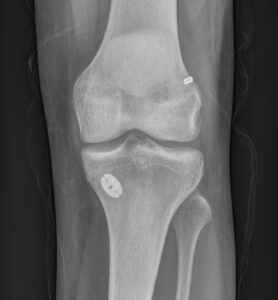

Knee Procedures Total Knee Replacement A knee replacement is a surgical procedure in which damaged or worn-out parts of the knee joint are removed and replaced with artificial components. It is typically done to reduce pain and improve function in people with severe knee joint damage, often caused by arthritis or injury. Partial Knee Replacement A knee replacement is a surgical procedure in which damaged or worn-out parts of the knee joint are removed and replaced with artificial components. It is typically done to reduce pain and improve function in people with severe knee joint damage, often caused by arthritis or injury. Revision Knee Replacement Revision knee replacement is a surgical procedure to replace or repair a previous knee prosthesis that has become loose, worn out, or infected. It involves removing the old implant and installing a new one to restore knee function and relieve pain. High Tibial Osteotomy High tibial osteotomy is a surgery that involves cutting and reshaping the upper part of the shinbone (tibia) to realign the knee joint. It is often performed to relieve arthritis pain in young, active patients by shifting weight away from damaged cartilage. ACL Reconstruction ACL reconstruction is a surgical procedure to replace a torn anterior cruciate ligament (ACL) in the knee with a graft, usually taken from the patient's own tissue or a donor. It aims to restore stability and allow return to normal activity levels following ligament injury. Meniscal Surgery Meniscal surgery involves repairing or removing damaged meniscal cartilage in the knee, which cushions and stabilizes the joint. The procedure can help relieve pain, restore knee function, and prevent further joint degeneration. Patellofemoral Stabilisation Patellofemoral stabilisation is a procedure to realign or secure the kneecap (patella) when it tends to dislocate or drift out of place. It aims to improve knee stability and prevent recurrent dislocations or pain.